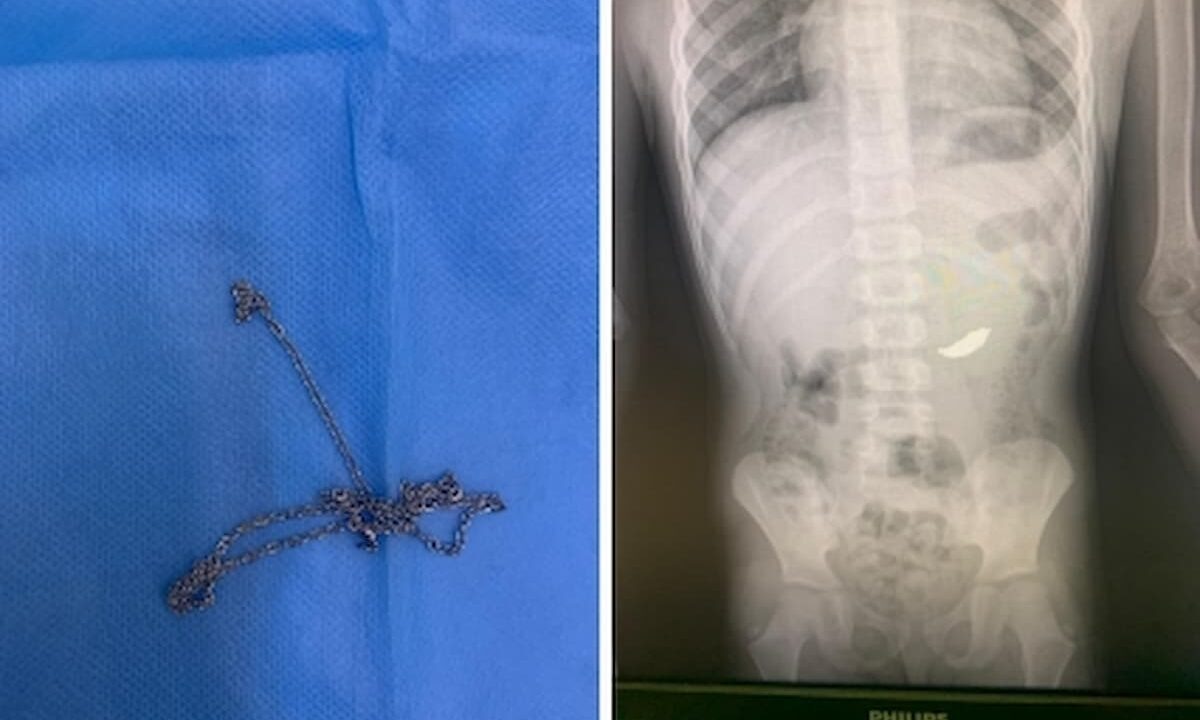

Ребенка экстренно госпитализировали ночью 13 мая в отделении эндоскопии Туапсинской районной больницы № 1.

Мальчику требовалась срочная процедура по извлечению из желудка инородного предмета. После рентгена оказалось, что в желудке ребенка находится цепочка. Медики предположили, что цепочка могла проскользнуть в пищевод на вдохе, если у ребенка была привычка держать ее во рту.

«К счастью, у нас уже большой опыт по безоперационному извлечению проглоченных предметов, да и оборудование отличное! Так что все прошло хорошо, состояние ребенка удовлетворительное», — цитирует заведующего отделением эндоскопии Туапсинской районной больницы № 1 Гора Саакяна Telegram-канал газеты «Туапсинские вести».